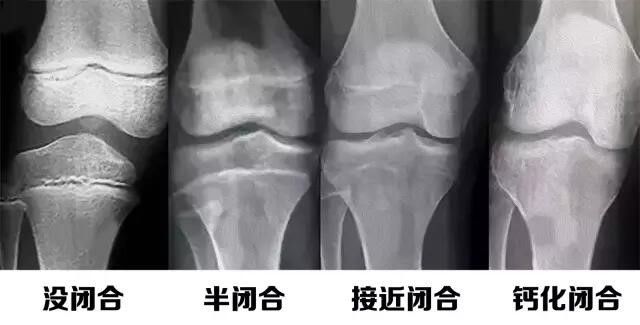

人之所以長高,是通过骨骼不断增長实現的,主要体現在長骨的不断增長,長骨由骨干和骨骺组成,骨干和骨骺间有一层软骨,叫骺软骨,又叫骨骺线。骺软骨在生長激素的刺激下不断分裂增殖,骨细胞不断增多并不断骨化,人就不断長高。

所以,人长高需要两个条件,一个是脑垂体分泌足量的生长激素,一个是骨骺线没有闭合。

在同等因素下的两个孩子,从出生到骨骺线闭合期间,年龄在不断地增长,骨骼也在不断地成熟。在这期间,生长激素分泌的多少决定了这两个孩子的身高。生长激素分泌充足的孩子,满足了身体生长所需,身体会长得高,反之分泌不足的孩子会出现生长缓慢,最终可导致身材矮小。身高的增长不是无限的,骨骼会随着年龄的增长不断的成熟,而骨骺线随着骨骼的不断成熟由宽变窄直至闭合,当骨骺线闭合之后,身体将停止生长,身高最终定格,高矮差距也就此形成。

要孩子在0~19岁的成长期,

骨骺线没有闭合

一切就来得及!